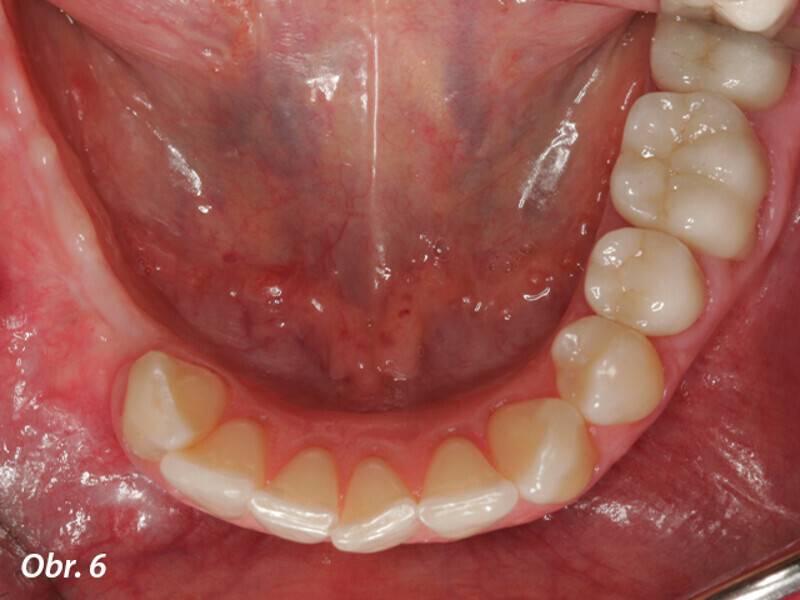

Horizontální augmentace hřebene a implantace: Dvoufázová procedura GBR